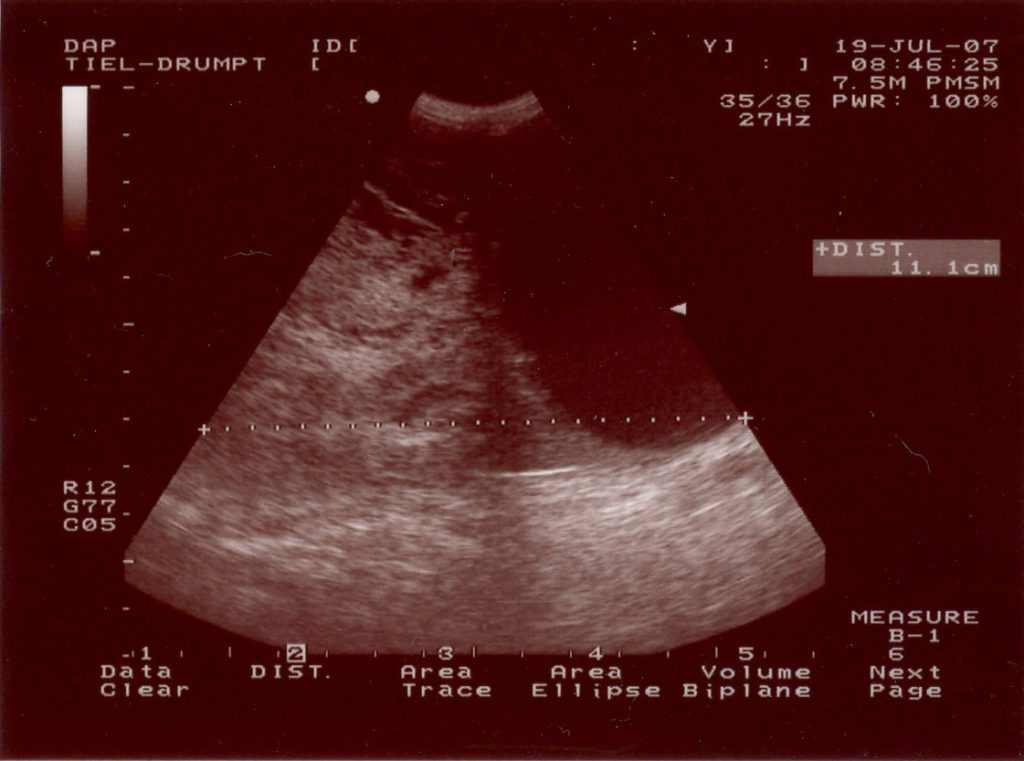

Duco is een 9 jaar oude Duitse Herder uit Tiel die sinds 1 dag toonde als een zieke hond. Hij wilde niet gaan liggen, had geen rust, was veel aan het hijgen. Bij het algemene onderzoek ontdekte de dierenarts een forse dikte in de buik. Om meer informatie over de aard van de dikte te krijgen, hebben we een echo gemaakt. We keken naar de structuur en keken of er meer loos was in de buik dan alleen deze ene bult (bijvoorbeeld uitzaaiingen van een tumor).

Aangezien Duco maar 1 testikel in zijn scrotum had (en de andere testikel dan in bijna alle gevallen in de lies of in de buikholte is ‘blijven steken’, een zogenoemde binnenbal ofwel een cryptorche testikel), was er de verdenking van een tumoreuze verandering van de testikel in de buik. (wanneer testikels in de buik of in de lies zitten zullen ze sneller tumoreus ontaarden door de hogere omgevingstemperatuur).

Hieronder ziet u een aantal foto’s van de operatie: